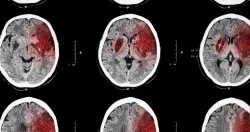

Computed tomography (CT or CAT scan) is an X-ray technique that uses a computer to create cross-sectional (or slice-like) pictures of your brain. A CT scan can show whether you have had a stroke. A CT scan can also help doctors identify the type of stroke you have had—ischemic (the result of a blockage) or hemorrhagic (the result of bleeding).